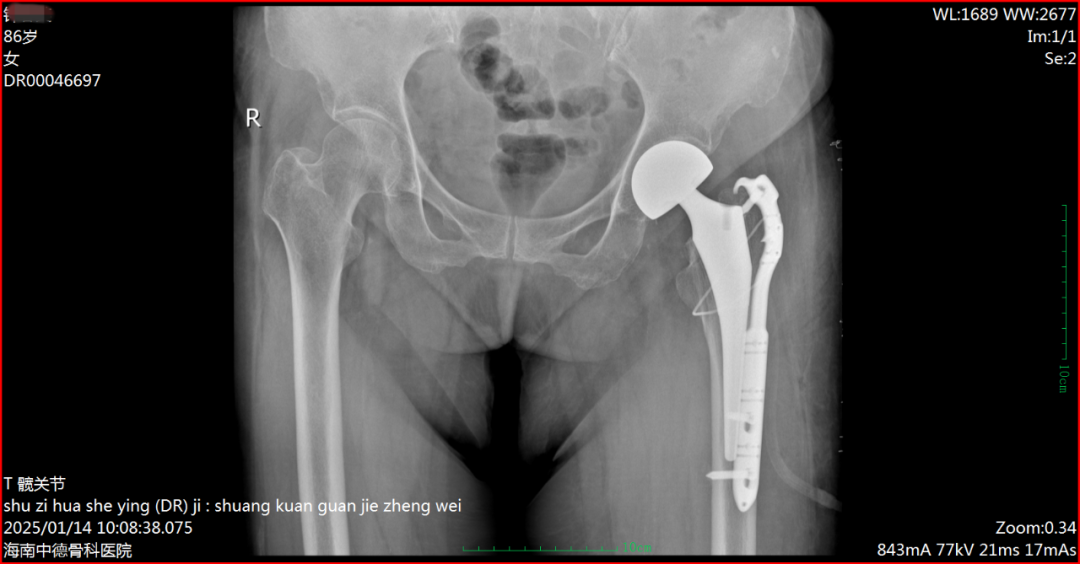

术前DR片 (86岁钟阿婆)

患者钟阿婆今年86岁,2年前因左侧股骨头坏死在我院做过“左侧人工股骨头置换术”,术后恢复良好。今年1月初在家意外摔倒,臀部着地,当即不能站立,入院查体确诊:左股骨假体周围骨折,伴高血压、糖尿病、陈旧性脑梗。